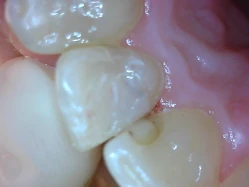

Hình 6: Chú ý mối hàn composite phía xa răng 11 hoàn toàn thấy được trên lâm sàng nhưng trên X-quang lại là một vùng thấu quang. Một mối hàn khác trên răng 12 kế cận mới hơn mối hàn trên răng 11, và nó cản quang.